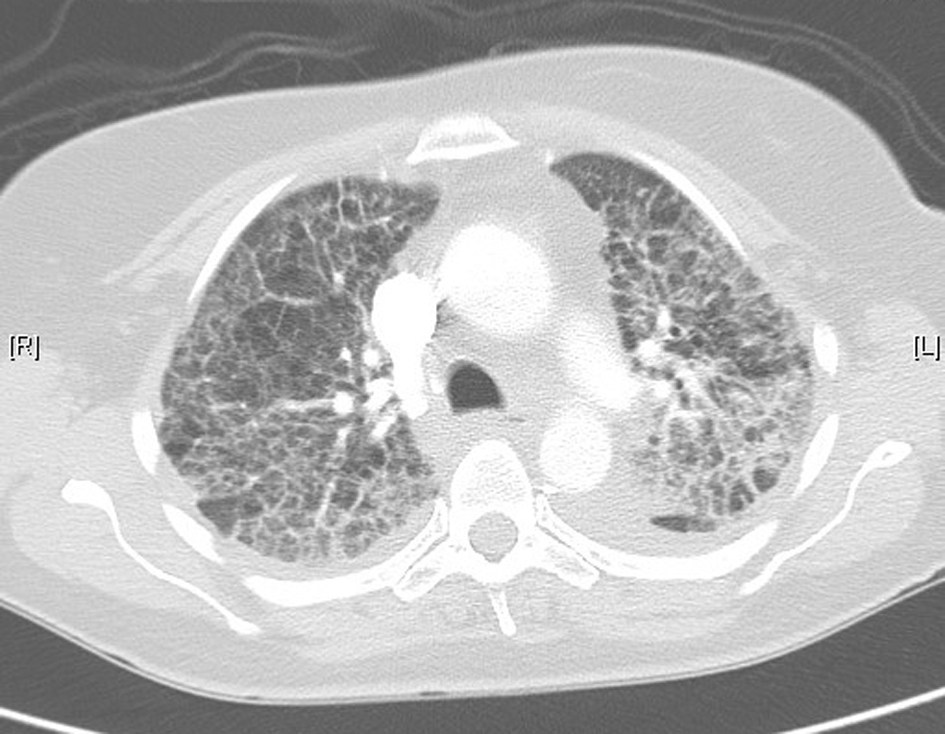

In November 2012, 13 days after the second dose of pemetrexed, the patient presented to our tertiary referral center after developing fever, cough, lethargy and dyspnoea at rest. She had no chest pain or pedal edema. On initial examination, the patient was febrile (temperature 38 °C) and in visible respiratory distress with a respiratory rate of 30 breaths/min and oxygen saturation 78% on room air. An arterial blood gas analysis taken on 8 L/min of oxygen showed hypoxia with a respiratory alkalosis (pH 7.47, PO2 73 mm Hg, and PCO2 32 mm Hg). Chest X-ray showed diffuse reticulonodular opacities in the upper lobes bilaterally (Fig. 2). CT scan revealed widespread interstitial opacity with inter- and intra-lobular septal thickening, and fine nodularity throughout both lung fields (Fig. 3). In some regions the diffuse interstitial opacity gave a ground glass appearance. The radiological changes were diffuse, including areas outside of the previous radiotherapy field. There was no evidence of pulmonary embolus. Her white cell count was not elevated (4 × 109/L; neutrophils 3.5 × 109/L) and hemoglobin level was 101 g/L. Tests of renal and liver function were normal. C-reactive protein was 170 mg/L (normal < 8 mg/L). She was commenced on broad spectrum intravenous antibiotics and transferred to the intensive care unit (ICU) due to ongoing hypoxia and respiratory distress. In the ICU she was commenced on intravenous dexamethasone and placed on non-invasive ventilation. She improved rapidly over the next 3 - 4 days. Repeated blood cultures and induced sputum did not reveal evidence of a typical or atypical infective cause. Bronchoscopy was not performed as the patient was not fit for the procedure whilst acutely unwell. She improved rapidly with conservative management.

![]() Click for large image | Figure 3. Lung computed tomography during acute illness, showing bilateral diffuse interstitial changes and ground-glass opacities. |